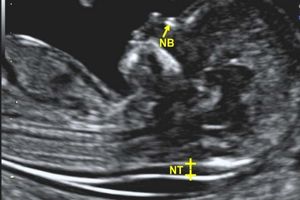

تشخیص بارداری: سونوگرافی یکی از روشهای استاندارد برای تأیید بارداری است. در این روش میتوان سن بارداری، تعداد جنینها، موقعیت جنین و وجود یا عدم وجود مشکلاتی مانند حاملگی خارج از رحم را بررسی کرد.

بررسی رشد و سلامت جنین: سونوگرافی در طول بارداری برای بررسی وضعیت رشد جنین، سلامت قلبی-عروقی آن و بررسی مشکلات احتمالی مانند نقصهای مادرزادی استفاده میشود.